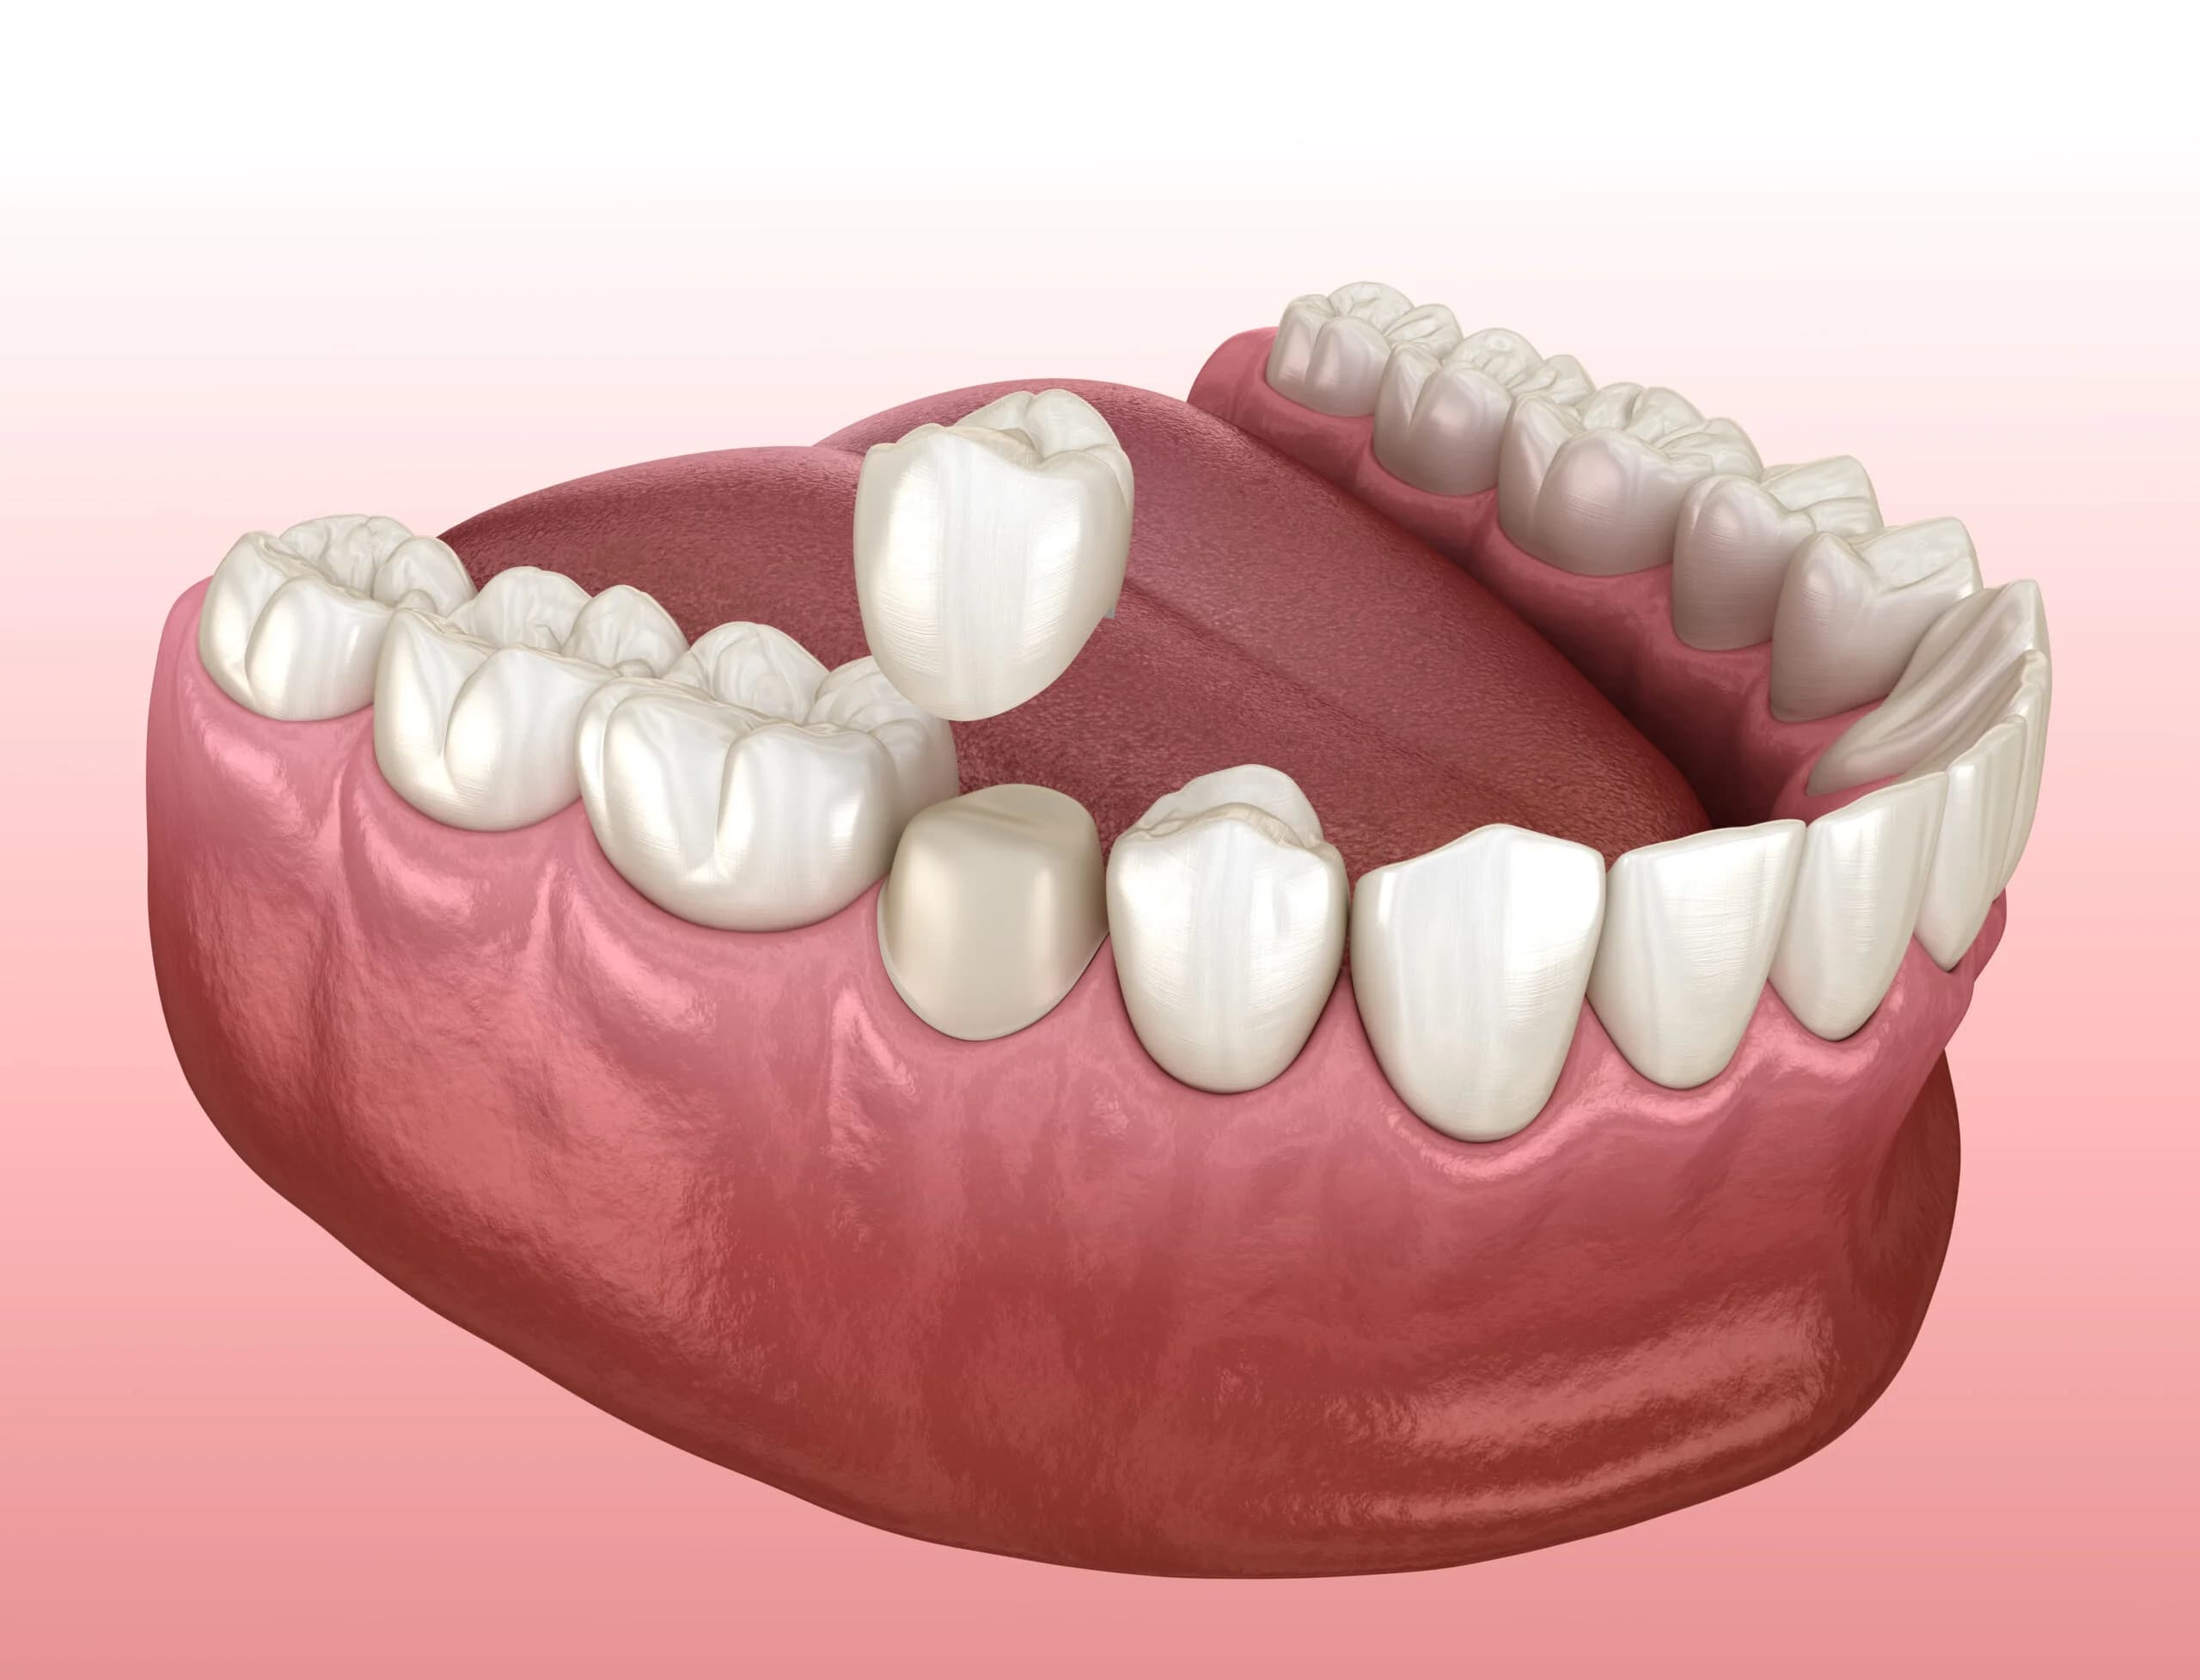

Bridges

Dental bridges are used to replace a single missing tooth or a row of missing teeth. A bridge consists of artificial teeth with dental crowns on either side. The natural teeth on both sides of the gap will be shaven down then the bridge is bonded to your natural teeth. The crowns fit over your natural teeth and the artificial teeth span the gap in between them.